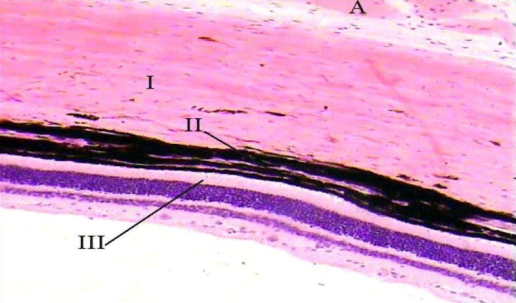

37 Задняя стенка глаза:

Полый оболочечный слоистый. 3 оболочки: 1 – Склера (ПВСТ оформл.);2 – Сосудистая оболочка ( РВСТ, кровеносные сосуды и меланоциты); 3-Сетчатая ( нервная ткань и пигментный эпителий) – имеет 10 слоев, в препарате видим: Пигментный слой( кл. кубические); палочки и колбочкинар.ядерный ( ядра палочек и колбочек); нар. сетчатый ( аксон палочек и колбочек, дендриты биполярных),внут.ядерный(тела биполярных);внут.сетчатый(аксоны биполярных, дендриты ганглионарн.); ганглионарный(ганглионарные клетки); слой нервный волокон( аксоны ганглионарных клеток)

Имеются также горизонтальные и амакринные клетки (тормозные)

Глия: олигодендроглия, микроглия, клетки Мюлера.